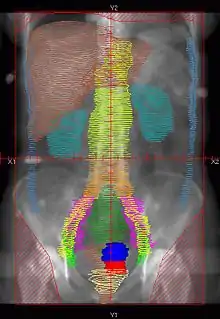

RT Technique

- There are multiple techniques, but typically Whole Abdomen RT is given to 22.5-25 Gy, followed by boost to PA LNs and whole pelvis to 45-50.4 Gy

- Dose: 22.5-25Gy in 130-150cGy/fx.

- Simulation: Supine with Alpha cradle.

- Fields: AP/PA single fields or 4-field technique

- Blocks:

- Kidneys – 50% transmission block or block after 15Gy.

- Liver – Block at 25Gy. Block not used by some institutions.

![]() |

Example of a AP whole abdomen/pelvis radiation therapy treatment field used at Tufts/Brown residency program. Actual patient contours should guide field design.